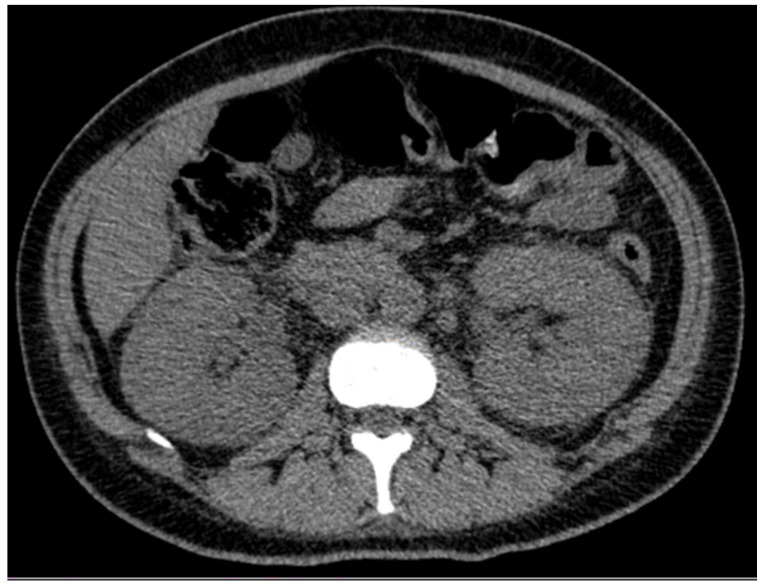

摘要:肾斑疹是一种罕见的慢性肉芽肿性疾病,常伴有免疫抑制和持续的革兰氏阴性感染,尤其是大肠杆菌。病例介绍:我们报告一例31岁女性高血压,妊娠期糖尿病,引产后子宫刮除为先兆子痫在23周。术后出现尿脓毒症。影像学显示双侧肾肥大,实验室检查显示急性肾损伤(KDIGO III期)、贫血和血小板减少症。血液和尿液培养培养出大肠杆菌。肾活检证实斑疹,显示pas阳性Michaelis-Gutmann小体和Von Hansemann细胞。患者对长期抗生素治疗和支持性护理有反应。讨论与结论:本病例强调了在非典型尿路感染和肾脏病患者中考虑肾脏畸形的重要性,特别是在产科环境中。组织病理学确认是必要的,及时使用细胞内活性抗生素治疗可导致良好的结果。早期诊断对预防不可逆肾损害至关重要。

Introduction: Renal malacoplakia is a rare chronic granulomatous disease, often associated with immunosuppression and persistent Gram-negative infections, particularly Escherichia coli. Case Presentation: We present a case involving a 31-year-old woman with hypertension, gestational diabetes, and prior uterine curettage after labor induction for preeclampsia at 23 weeks. She developed urinary sepsis post-procedure. Imaging revealed bilateral nephromegaly, while laboratory tests showed acute kidney injury (KDIGO stage III), anemia, and thrombocytopenia. Blood and urine cultures grew Escherichia coli. Renal biopsy confirmed malacoplakia, demonstrating PAS-positive Michaelis-Gutmann bodies and Von Hansemann cells. The patient responded to prolonged antibiotic therapy and supportive care. Discussion and Conclusion: This case highlights the importance of considering renal malacoplakia in patients with atypical urinary tract infections and nephromegaly, particularly in obstetric settings. Histopathological confirmation is essential, and timely treatment with intracellularly active antibiotics can lead to favorable outcomes. Early diagnosis is critical to prevent irreversible renal damage.